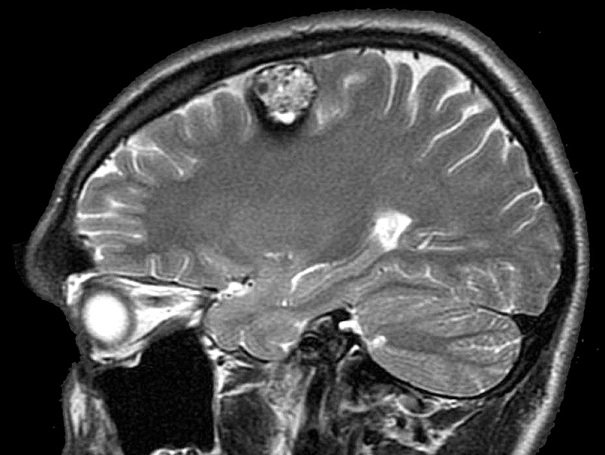

Врачи отмечают, что каверномы головного и спинного мозга представляют собой сосудистые аномалии, которые могут вызывать разнообразные неврологические симптомы. Специалисты подчеркивают, что многие пациенты остаются бессимптомными на протяжении долгого времени, что затрудняет диагностику. Однако при наличии симптомов, таких как головные боли, судороги или неврологические дефициты, важно провести тщательное обследование. Врачи рекомендуют использовать магнитно-резонансную томографию для точной визуализации каверномы и оценки ее размера и расположения. Лечение может варьироваться от наблюдения до хирургического вмешательства, в зависимости от клинической ситуации. Важно, чтобы пациенты получали индивидуальный подход и консультации опытных специалистов для выбора оптимальной стратегии лечения.

Диагностика каверномы

Данная патология диагностируется с помощью следующих исследований:

- МРТ помогает установить наличие каверн в спинномозговой и головномозговой структурах;